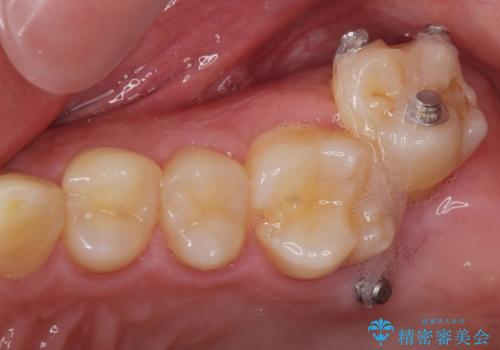

左上の奥歯がシザーバイトがありワイヤーで部分的な矯正を行い、シザーバイトを改善した後にインビザラインで全体的な矯正治療を行いました。

シザーバイトは歯と歯が噛み合っていないのでしっかり噛むように処置をする必要があります。